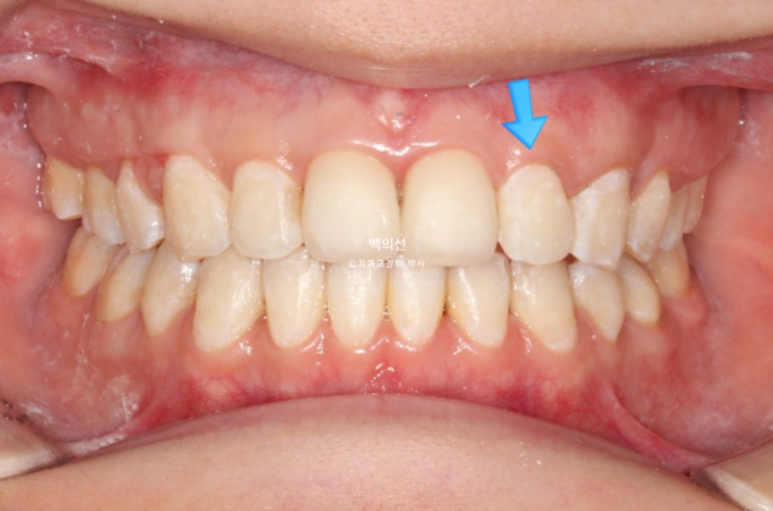

인비절라인 장치제작을 위해 클리피씨 장치를 제거한 직후입니다.

25.02

아직 맞지 않는 중심선은 남은 공간이 닫히면 자연스레 맞아질 것 입니다.

아까 엑스레이에서 치축이 기울어져 있던 파란화살표 측절치는 튀어나와 보이고 기울어져 보입니다.